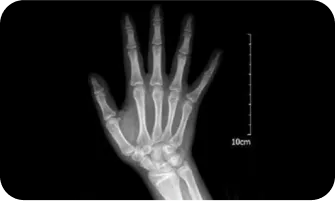

02

엑스레이 검사를 이용한

여아의 골연령검사

300점

400점

8.5세

500점

10세

600점

11세

700점

12세

800점

13 ~ 14세

900점

14 ~ 15세

1000점

15세 ~